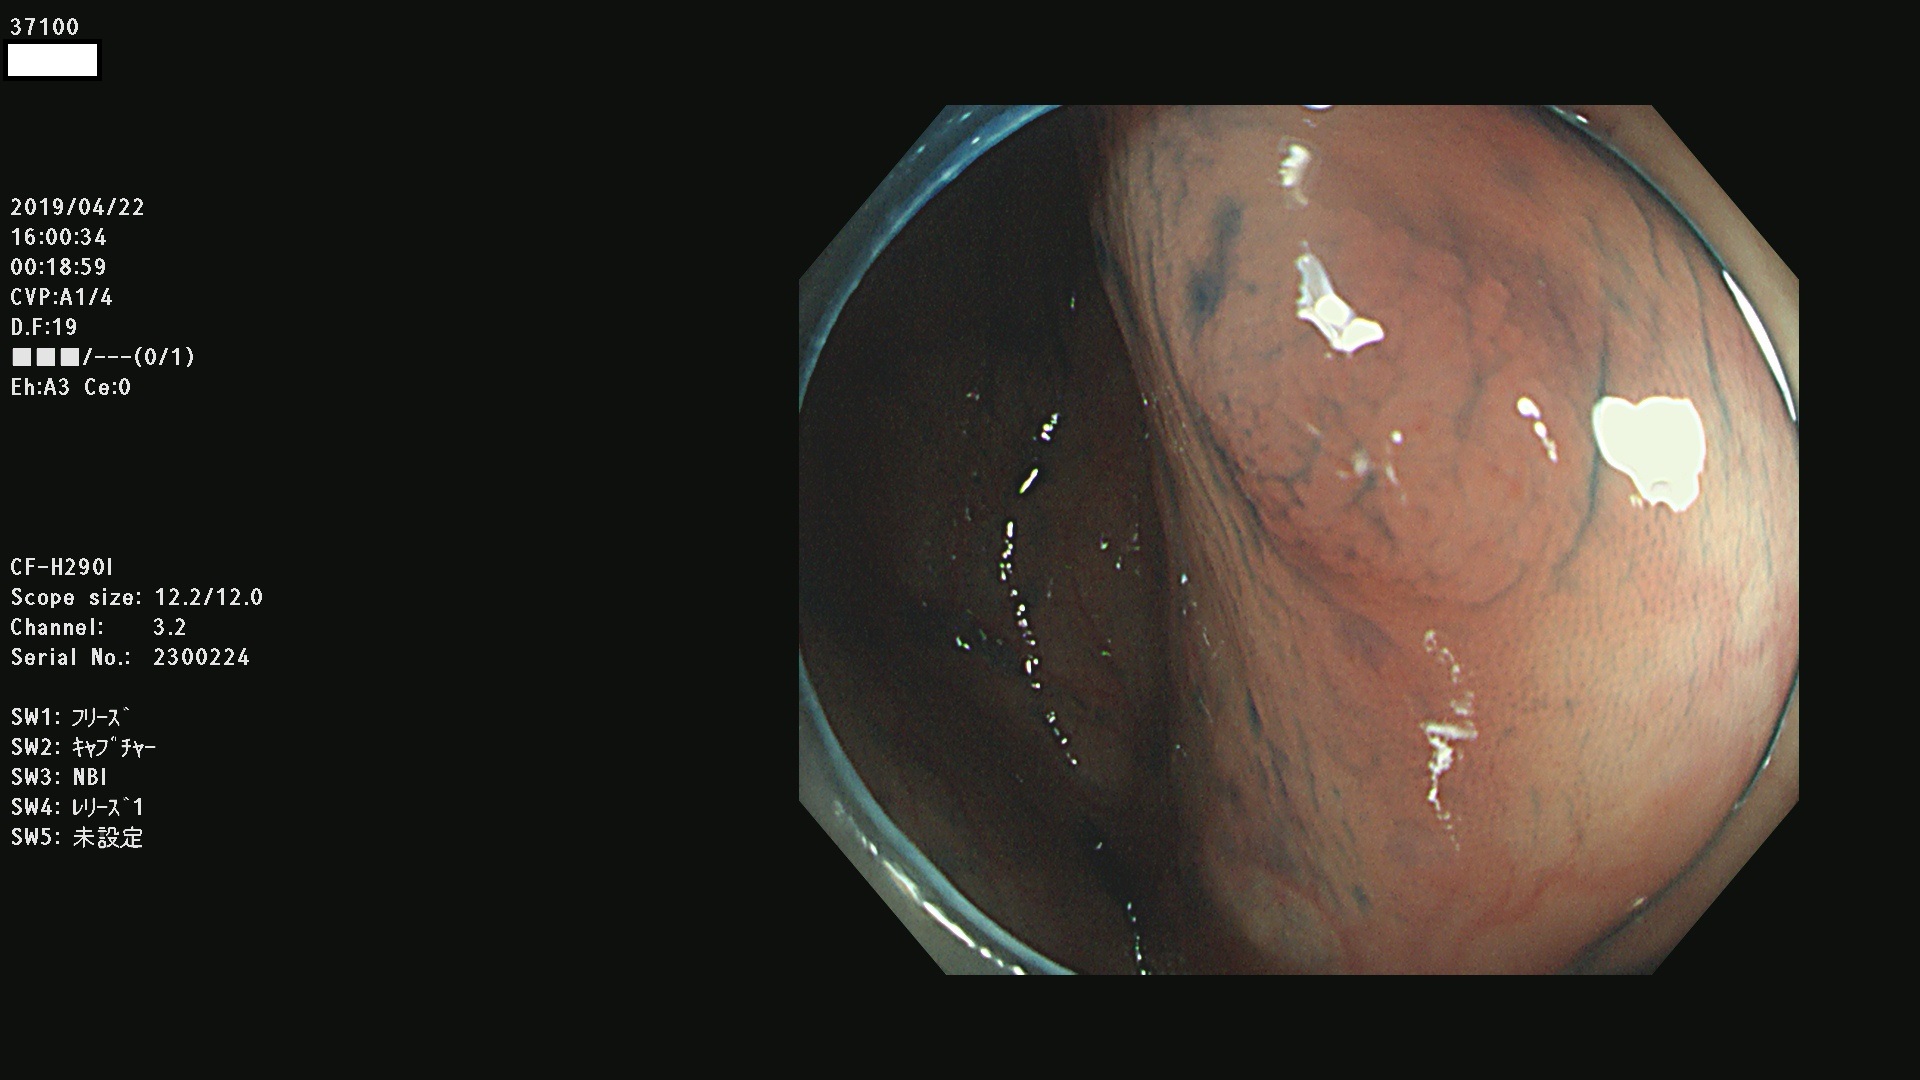

37100 37101 37102 37104 37106 37108 37110 37111 37112 37113 37115 37118(SSAPのみ) 37120 37122 37123 37124 37127(SSAPのみ) 37128(SSAPのみ) 37131 37132 37133 37134 37135 37139 37141 37142 37143 37144(SSAPのみ) 37145 37147(SSAPのみ) 37148 37149 37150 37153 37154 37157 37159 37161 37162 37163 37164 37165 37166 37167 37168 37169 37170 37171 37172 37173 37175(SSAPのみ) 37176 37177 37178 37180(SSAPのみ) 37181 37184 37185 37186 37187 37188 37189 37190 37192 37194 37197 37198

発見困難で危険性の高い平坦型病変(上記100名より抽出)